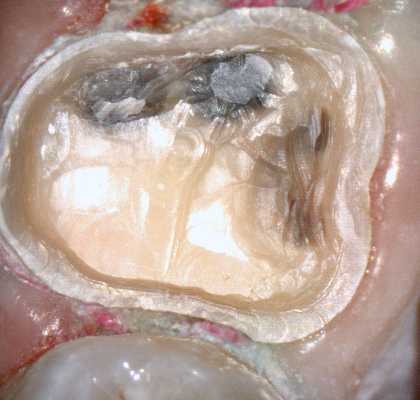

The following pictures depict the sequence of burs we recommend that you use to finish a preparation quickly. While patient is getting numb, take a quick look at the clearance you will need to reach proper material thickness. Once the quadrant is isolated with isolite and optragate, take an occlusal router bur and create a trough to gain the proper depth. Follow that with a flat disk, and you can quickly reduce the occlusal height.

A shoulder bur of .8 mm thickness can help you reduce the interproximal areas as well as the buccal and lingual margin lines. Before finishing the prep, place hemostatic agent like expasyl in the sulcus and place retraction cord. while it is setting, check your reduction. If you need more space, now is the time to reduce some more.